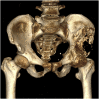

Introduction: and importance: Pelvic osteosarcoma is quite rare and is a challenging task for orthopedic surgeons. This aim of this study is to present the first case report using customized 3D-printed prosthesis in Vietnam.

Case presentation: 57-year-old male was diagnosed with pelvic osteosarcoma. After neoadjuvant chemotherapy, we did limb-salvage surgery after partial pelvic resection. He had to undergo another surgery due to an infection complication that exposed part of the prosthesis. At 6 months follow-up, the patient's overall status was stable. VAS score when moving is 2/10. He can walk with one crutch. Patient is still being followed up and treated.

Clinincal discussion: Management of pelvic osteosarcoma remains a challenging task for orthopedic surgeons. Advancements in customized 3D-printed prosthesis have been applied in treatment of pelvic osteosarcoma. Despite the complications, the results are promising. We believe that this is a new and innovative route in surgery of pelvic osteosarcoma.